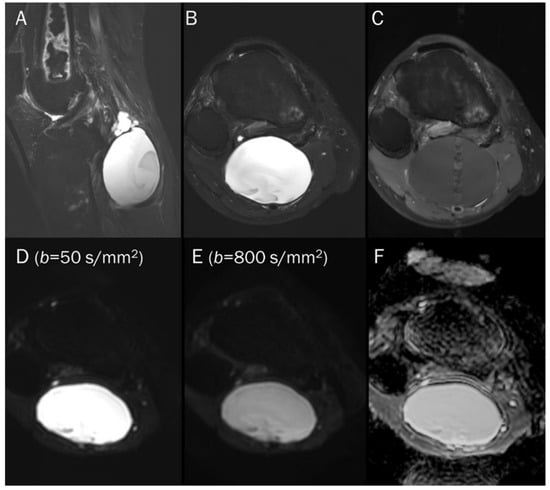

7.1. Cyst